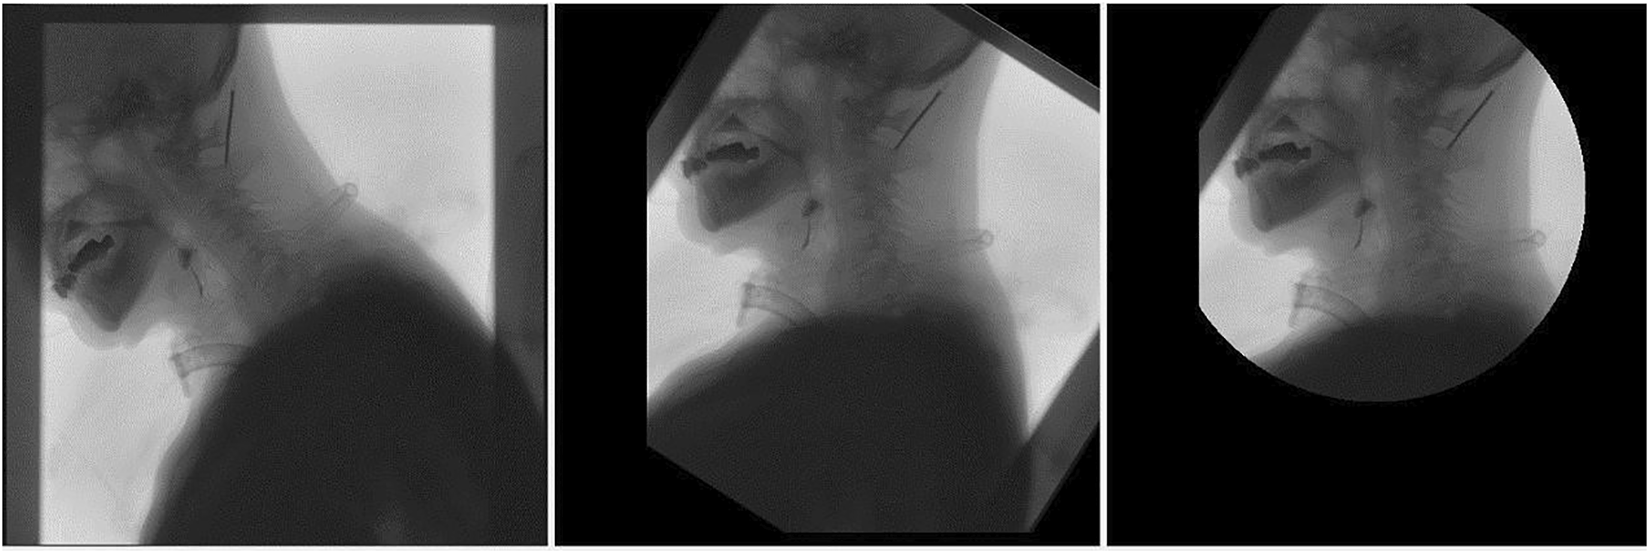

2.2.1 Image Rotation

Image preprocessing is image rotation. The purpose is to establish a new coordinate system based on the spine in each frame, maintain the fixation of the body, and better judge the movement of barium meal relative to various tissues and organs. The rotation center of the image is